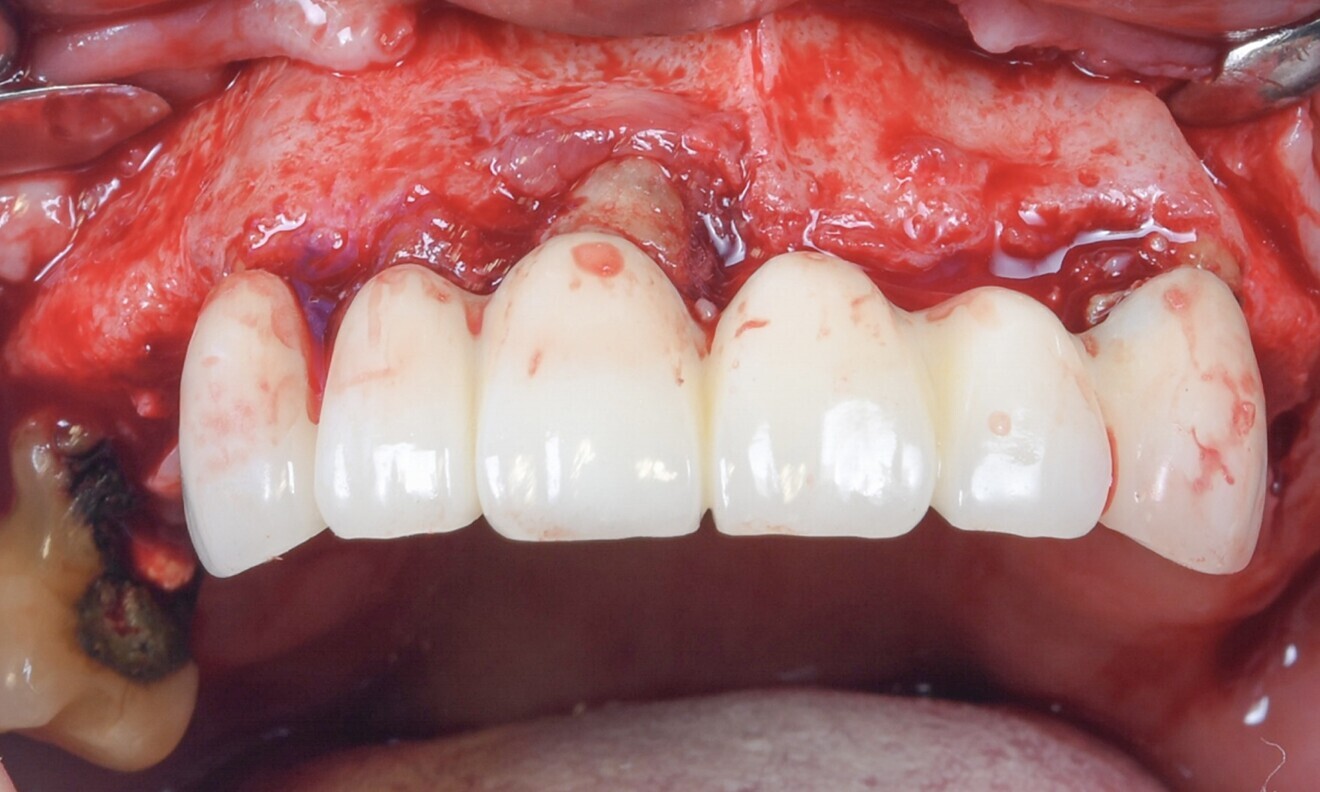

Prior to the surgical procedure, a careful assessment was conducted to ensure the precise fitting of the surgical guide. Subsequently, local anaesthesia using 2% lidocaine with 1:100,000 adrenaline was administered. An open flap access was performed with mid-crestal and intrasulcular incisions (Fig. 4). Next, the bone reduction guide was placed, and the holes for the anchor pins were drilled and the pins securely inserted (Fig. 5).

The bridge was removed, the teeth were atraumatically extracted and the extraction sockets were meticulous curetted. After the dental extractions, a reduction of the vertical ridge was carried out (Fig. 6). Subsequently, the surgical guide was positioned to initiate the drilling procedure for the immediate implant placement (Fig. 7).

Fig. 4